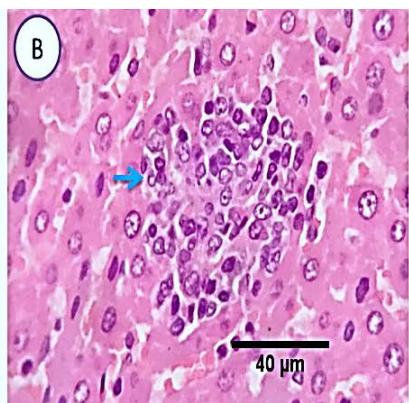

Liver: Sections from liver of this group denoted moderate portal biliary proliferation, congestion of portal blood vessels, round cell infiltration, multifocal interstitial lymphocytic and macrophages aggregations replacing previous necrotic patches beside degenerative changes in a few hepatocytes. (Fig.10)

Fig. 4: Photo-micrograph from liver, group (4), showing, portal biliary proliferation (A, yellow arrow, B, black arrow), congestions of portal blood vessels(A, black arrow), round cell infiltration and interstitial lymphocytic and macrophages aggregations replacing previous necrotic patches (B, blue arrow). Scale bars 120, 40, 40 um.